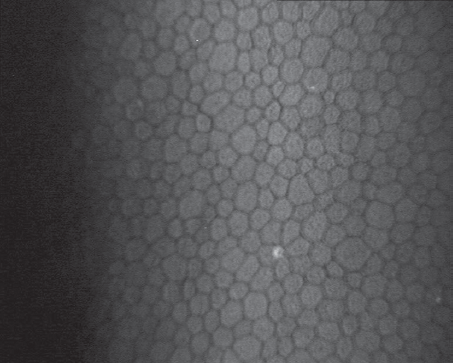

Fig. 4. Confocal microscopy, endothelial cells after YAG-laser activation of trabecular meshwork

Рис. 4. Конфокальная микроскопия, эндотелиальные клетки через 6 мес. после YAG-лазерной активации трабекул